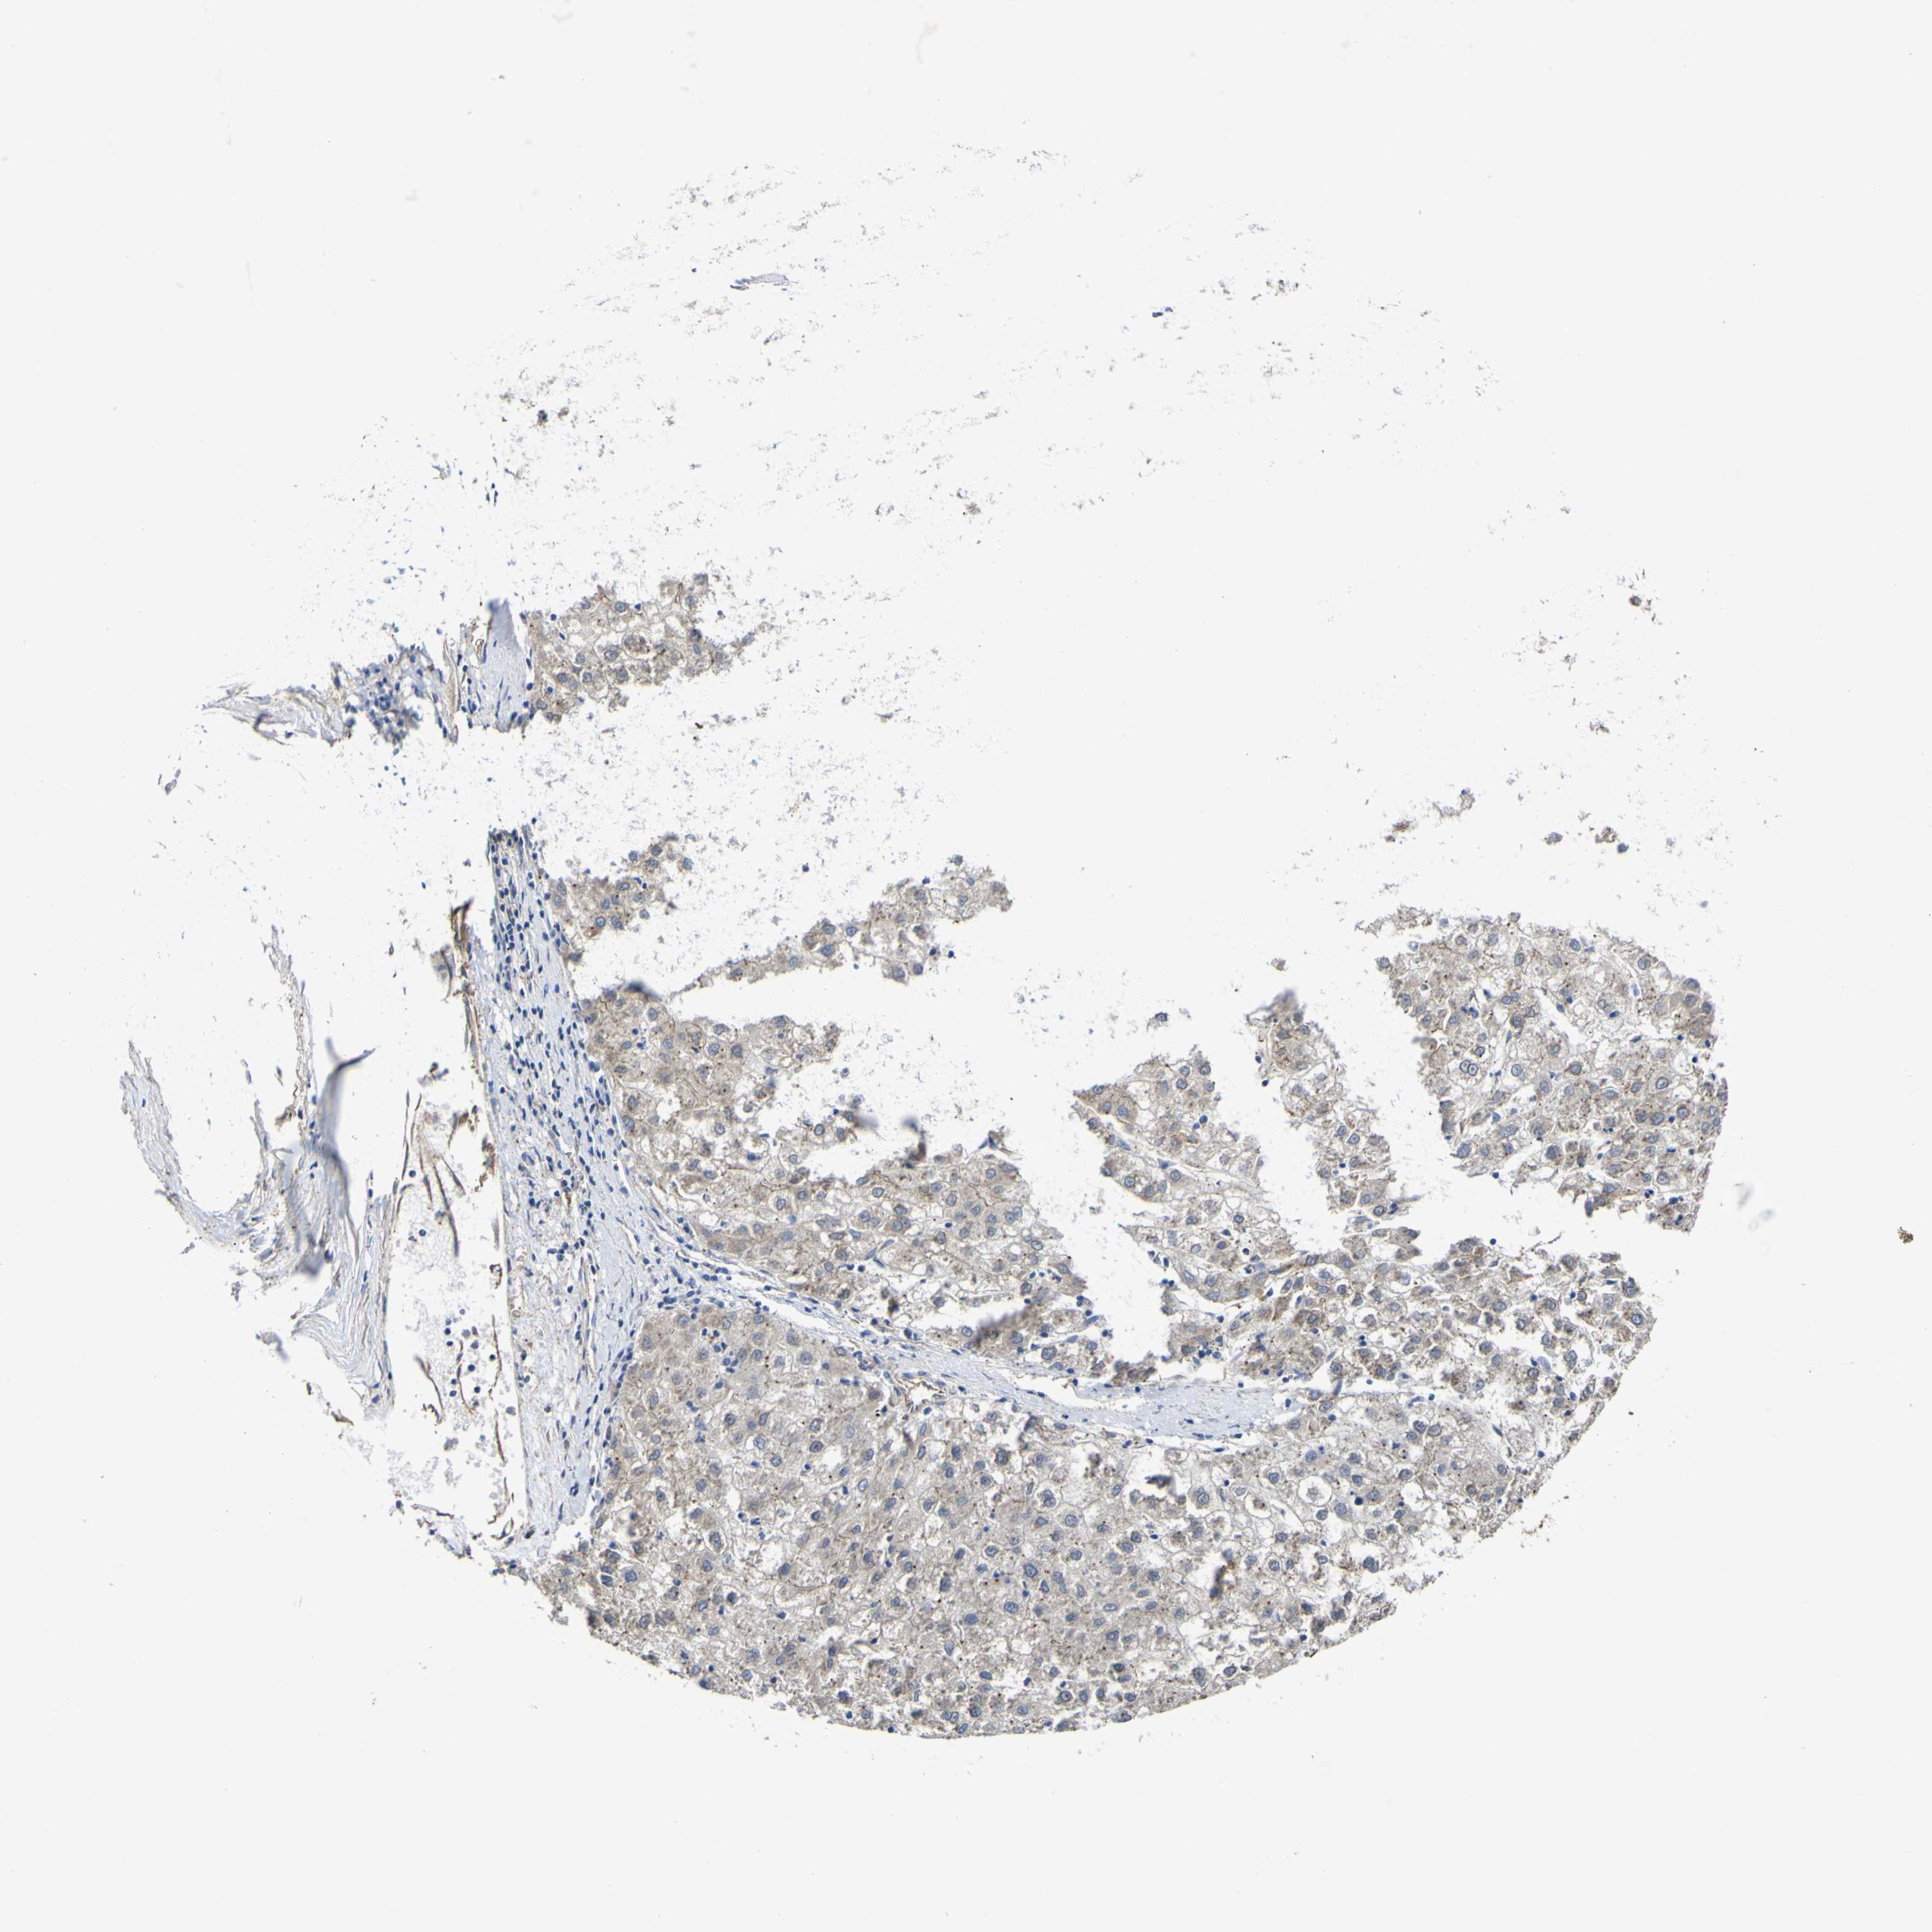

LIVER CANCER - Protein expressioni

A mouse-over function shows sample information and annotation data. Click on an image to view it in a full screen mode. Samples can be filtered based on level of antibody staining by selecting one or several of the following categories: high, medium, low and not detected. The assay and annotation is described here.

Note that samples used for immunohistochemistry by the Human Protein Atlas do not correspond to samples in the TCGA dataset.

Antibody stainingi

Antibody staining in the annotated cell types in the current human tissue is reported as not detected, low, medium, or high, based on conventional immunohistochemistry profiling in selected tissues. This score is based on the combination of the staining intensity and fraction of stained cells.

Each image is clickable and will lead to virtual microscopy that enables deeper exploration of all samples and also displays staining intensity scores, fraction scores and subcellular localization as well as patient and tissue information for each sample.

Antibody HPA012948

Staining

High

Medium

Low

Not detected

Intensity

Strong

Moderate

Weak

Negative

Quantity

>75%

75%-25%

<25%

None

Location

Nuclear

Cytoplasmic/membranous

Cytoplasmic/membranous,nuclear

Cholangiocarcinoma

Carcinoma, Hepatocellular, NOS